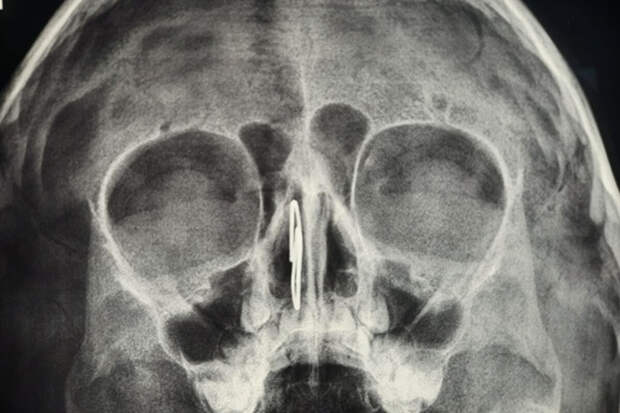

Врачи Областной детской клинической больницы во Владимире помогли четырехлетнему мальчику, который заигрался и засунул себе в нос скрепку. Об этом сообщили в пресс-службе медицинского учреждения.